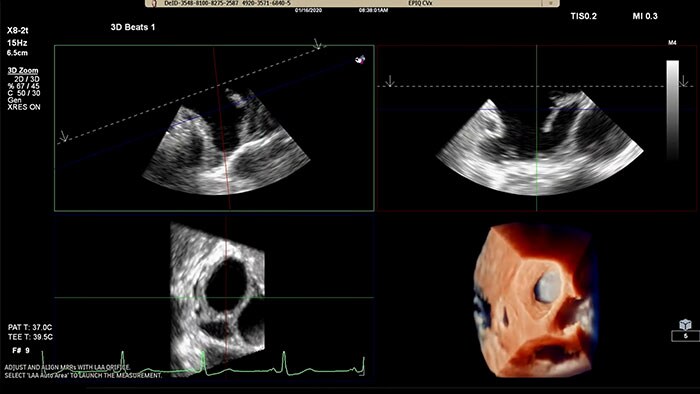

Rapidly acquire LAA orifice measurements in both traditional rendering or in TrueVue Glass rendering, with 3D Auto LAA